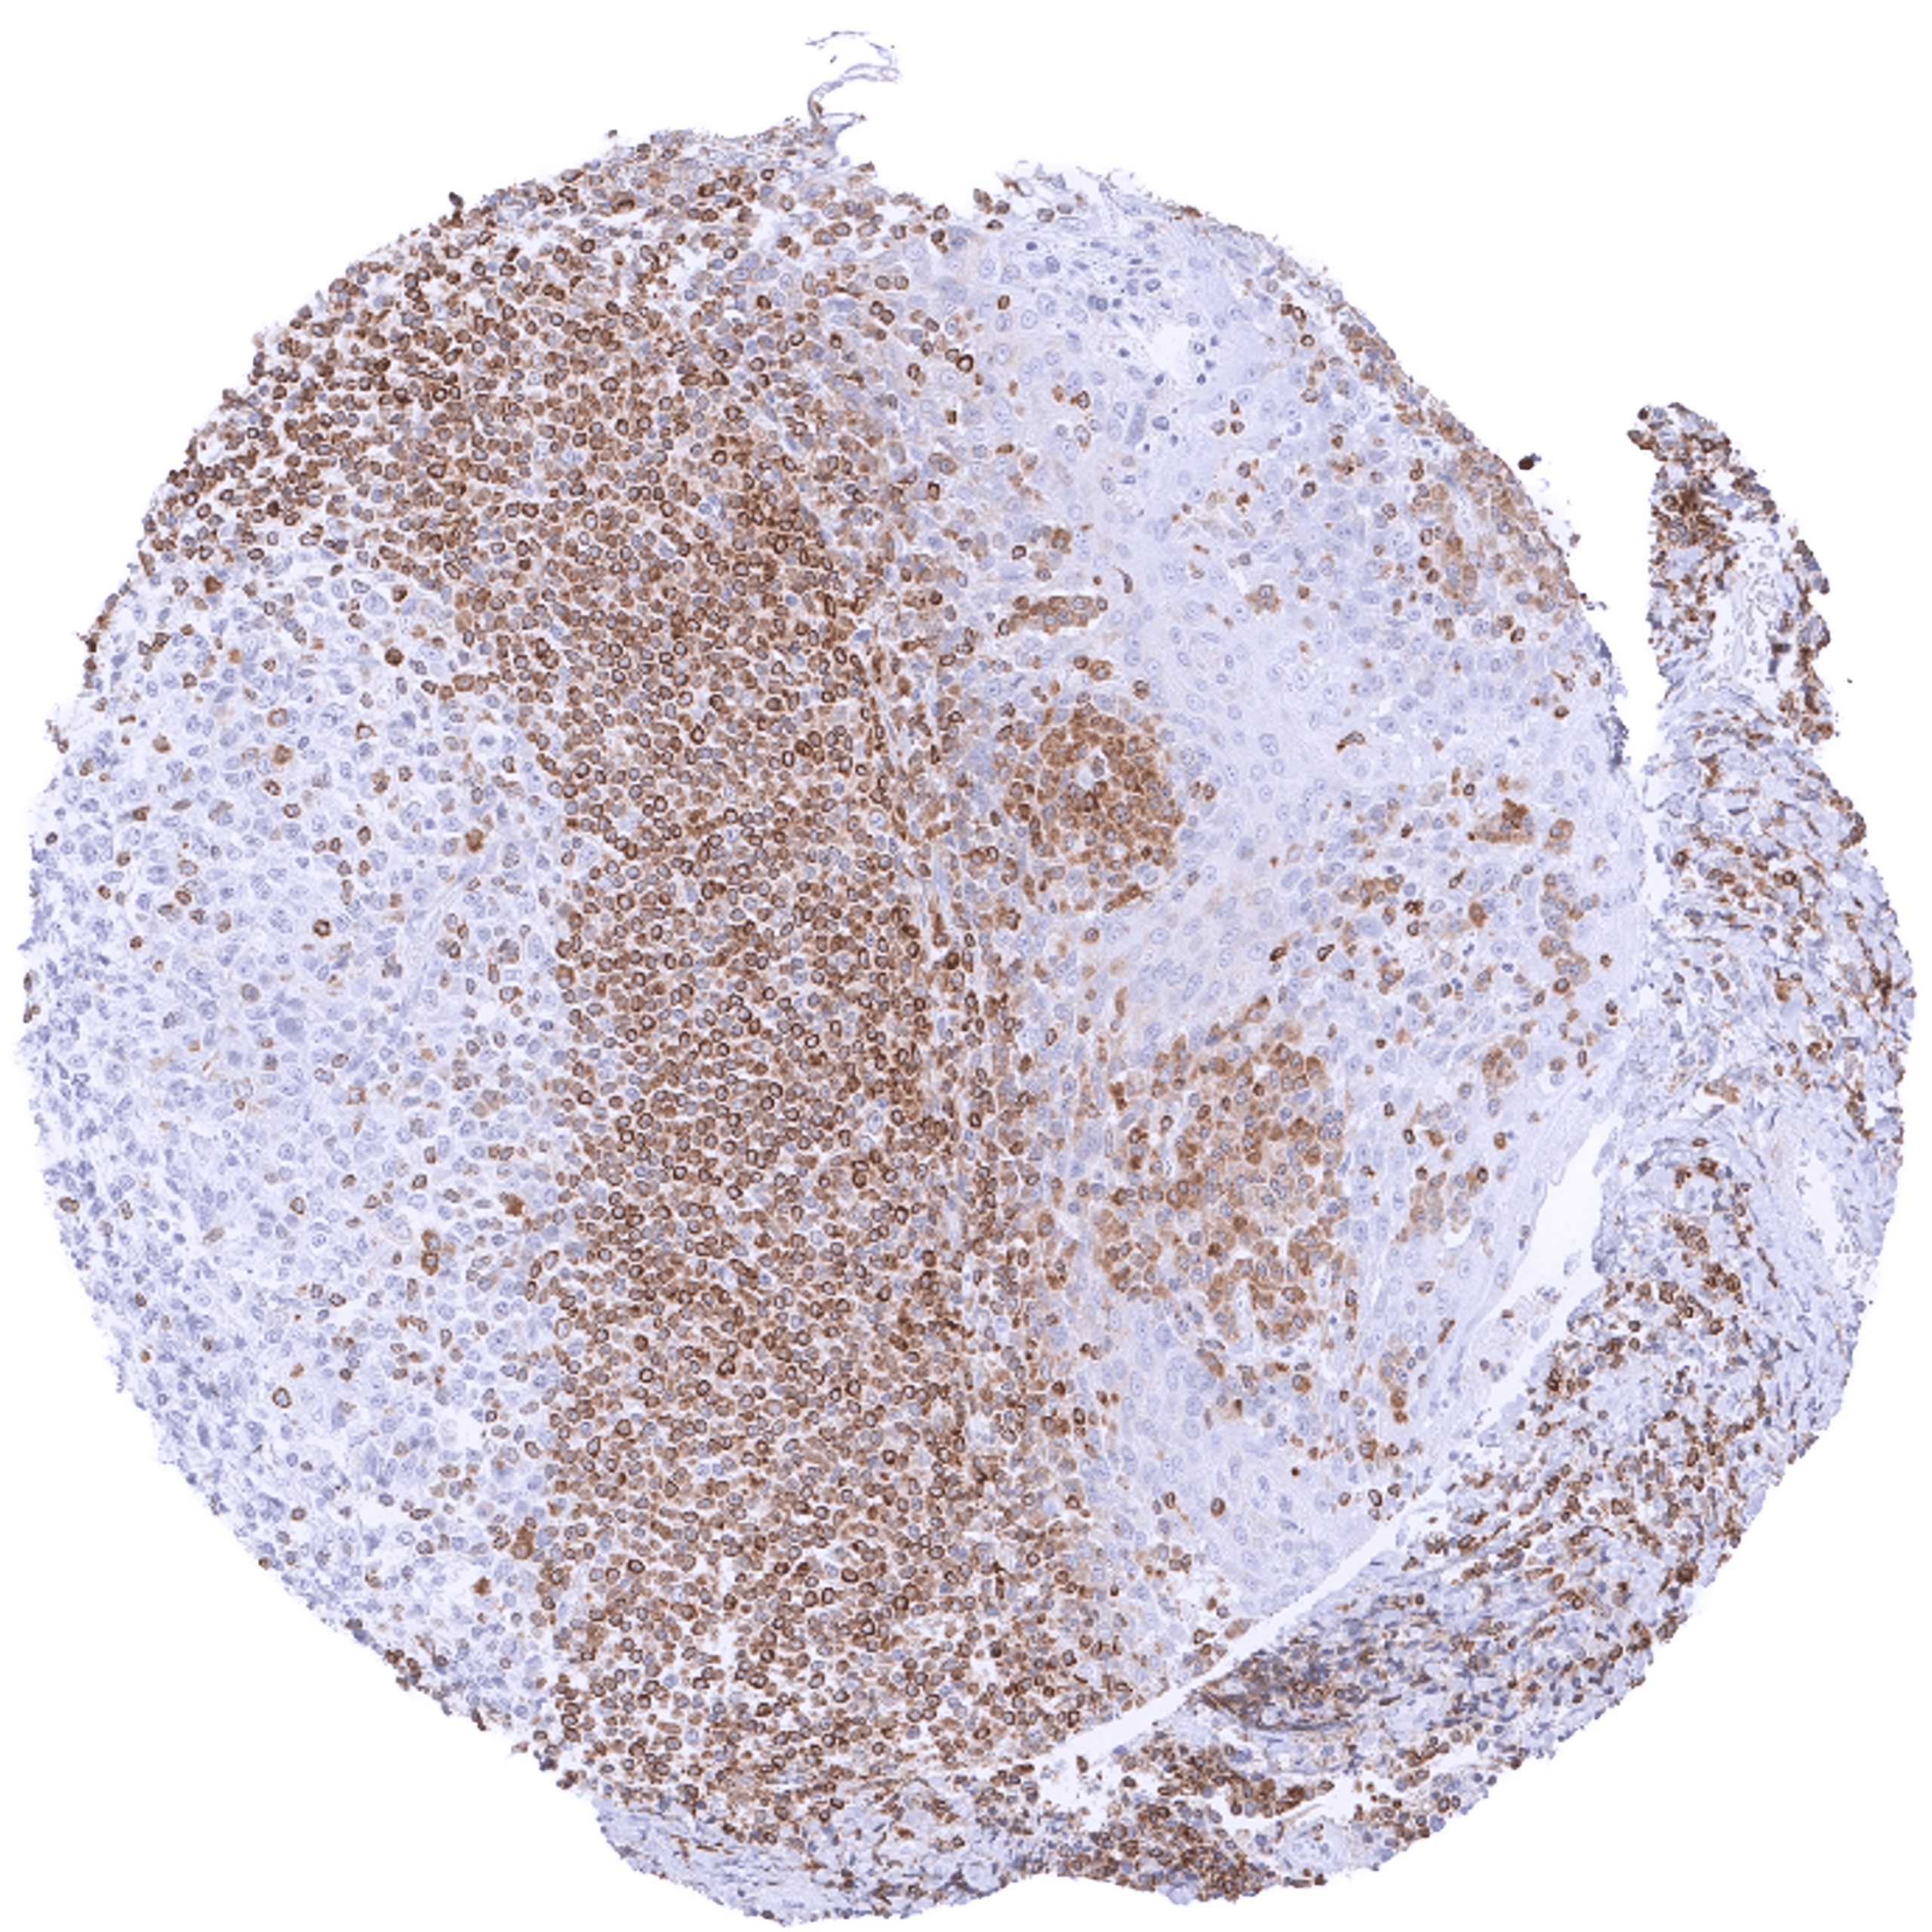

Positive control = Tonsil: A strong cytoplasmic bcl-2 staining should be seen in most interfollicular lymphocytes while most germinal centre cells are bcl-2 negative.

Negative control = Tonsil: The vast majority of lymphocytic cells from germinal centres must be bcl-2 negative while interfollicular lymphocytes are mostly positive.

| Tonsil | Strong bcl-2 positivity of a large fraction of lymphocytic cells in the interfollicular area and around germinal centres while almost all cells in germinal centres are bcl-2 negative. Squamous epithelium is bcl-2 negative although the basal cell layer may show weak positivity. | |